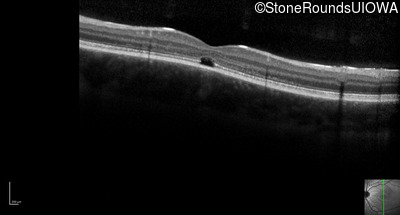

Optical Coherence Tomography - Right - 20/160 +2

Exemplar / OCT Stack

OCT Stack